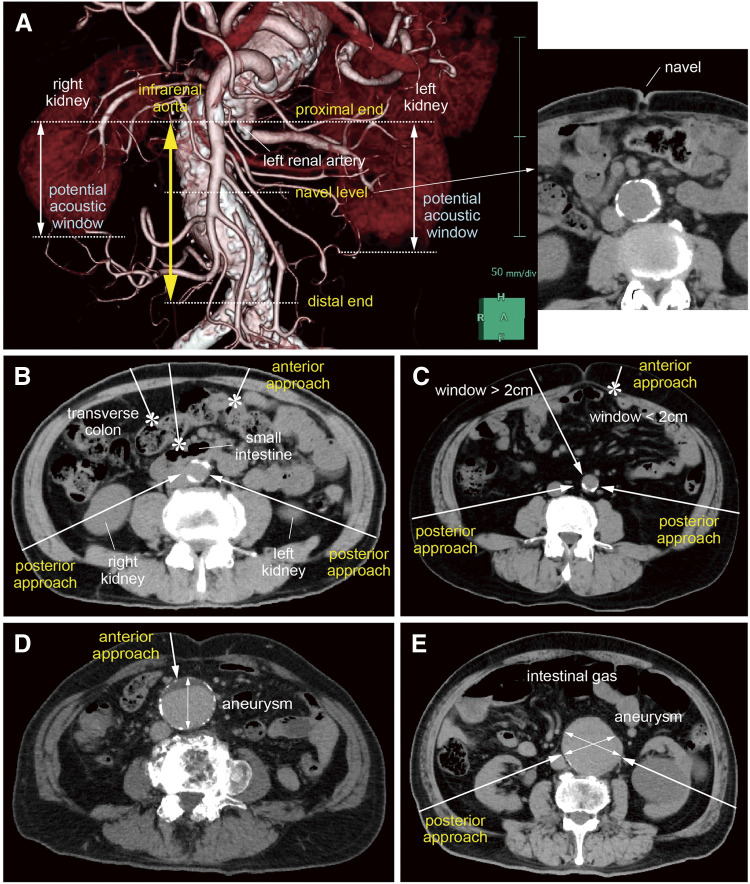

Objectives: With improved surgical outcomes for non-ruptured abdominal aortic aneurysm (AAA), the primary objective has shifted toward the detection of asymptomatic AAA. Since ultrasonographic visualization from the anterior abdominal wall is often obstructed by intestinal gas, utilizing additional bilateral posterior approaches via the retroperitoneal tissue may be beneficial. This study investigates the feasibility of assessment using three approaches through computed tomography (CT) data analyses. Methods: The study included 27 surgical patients with AAA (AAA group) and 37 patients with other atherosclerotic diseases (non-AAA group). CT data were analyzed to locate the infrarenal aorta relative to the navel, availability of acoustic window, depth of the aorta, and assessment of aneurysmal aorta using three approaches. Results: The "AAA area" for ultrasonographic screening may be set at 0-4 cm above the navel. An acoustic window was unavailable in 8.1% of AAA cases and 7.4% of non-AAA cases in the anterior approach; however, it was available in the posterior approach. Although the depth of the aorta was greater in obese patients, it remained within 20 cm. Conclusion: Ultrasonographic screening is feasible by incorporating posterior approaches in cases where anterior visualization is difficult, enhancing the detection of asymptomatic AAA.